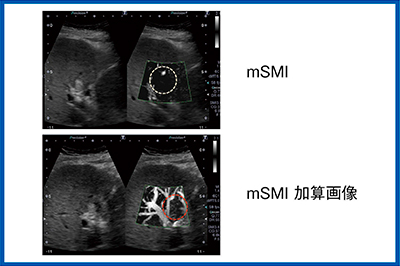

肝細胞がんの脈管・胆管浸潤

SMIは,肝細胞がんの脈管浸潤,胆管浸潤においても有用である。門脈にも浸潤している門脈腫瘍塞栓症例において,造影モードで門脈内に黒く抜けて観察される部分が,腫瘍塞栓なのか,血栓なのかを判別するためには,再度造影剤を静注して動脈性の栄養の有無を確認する。本症例のように,動脈血の流入があれば腫瘍塞栓と考えられる(図7)。